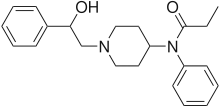

Anilidopiperidines